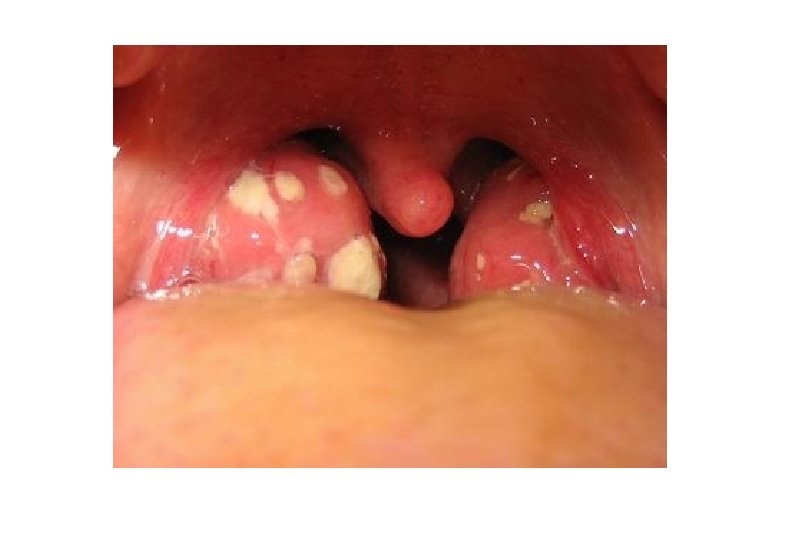

AMIGDALITIS ERITEMATOSA Y ERITEMATOPULTÁCEA q Inflamación de amígdalas con exudado purulento. q Afectación general, cefalea, apatía, dolor abdominal, adenopatía cervical q Etiología: - 50 % Vírica: Adenovirus, rinovirus, enterovirus, EBV. - 25 -40 % Bacteriana: Streptococcus b hemolitico grupo A

OTROS TIPOS DE AMIGDALITIS q Anginas pseudo-membranosas q Anginas Vesiculosas q Anginas ulcerosas q Anginas úlcero-necroticas

EXÁMENES COMPLEMENTARIOS q Test de diagnostico rápido Strepto-test q Cultivo Exudado faríngeo q Serología de EBV

Complicaciones q Adenitis y adenoflemones. q Flemón periamigdalar. q Complicaciones obstructivas q Síndrome de Grisel. q Infecciones regionales q Complicaciones generales

AMIGDALITIS y EXANTEMA Es un a asociación frecuente en caso de: q Enfermedad de Kawasaki q En alergia a medicamentos q En infección por EBV tratado con Penicilina q En la escarlatina

TRATAMIENTO q Sintomático: Analgésicos y antipiréticos (No se recomiendan antiinflmatorios ni corticoides por vía general) q Antibióticos (En caso de estreptococo): Ø -Amoxycilina 50 mg/kg/día 6 días Ø -Cefalosporinas 2ª-3ª generacion. Ø -Macrólidos en alérgicos a Penicilinas